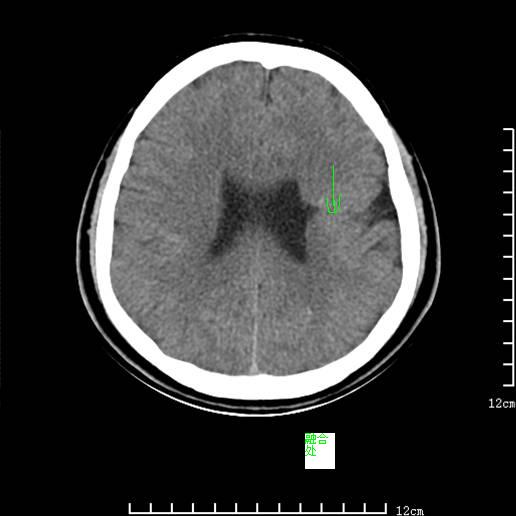

标题: CT13748:男,26岁,头部外伤。 [打印本页]

神清,语利。自小右侧上下肢肌力增强,呈痉挛状态。智力正常。

左侧大脑表面可见一裂隙延伸至侧脑室的室管膜下区,相应侧脑室外壁呈局限性峰状隆起,与裂隙相连,裂隙边缘可见密度较高的皮质结构 支持 考虑 脑裂畸形。

融合型脑裂畸形:表现为横贯大脑半球的灰质密度影,其外端分离,并分别与两侧皮层灰质相延续,局部蛛网膜下腔扩大;内端抵达脑室壁,并有分离,局部侧脑室呈三角形扩大。

典型脑裂畸形(开唇型)伴灰质移位.